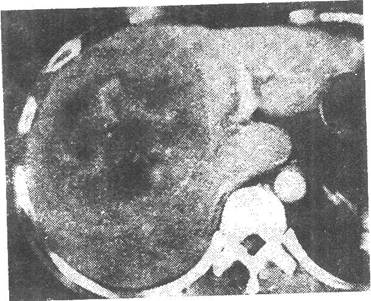

患者男性,49岁,发现乙肝十余年,反复腹痛,腹胀黄疸月余,CT图像如下,最有可能的诊断是( )。

门静脉期增强

[单选题]患者男性,49岁,发现乙肝十余年,反复腹痛,腹胀黄疸月余,CT图像如下,最有可能的诊断是( )。CT平扫动脉期增强门静脉期增强A.肝肉瘤B.肝血管瘤

[单选题]患者男性,49岁,发现乙肝十余年,反复腹痛,腹胀黄疸月余,CT图像如下,最有可能的诊断是( )。CT平扫动脉期增强门静脉期增强A.肝肉瘤B.肝血管瘤

[单选题]患者男,49岁。发现乙肝十余年,反复腹痛,腹胀黄疸1个月余,CT图像如下,最有可能的诊断是A.肝血管瘤B.肝再生结节C.肝癌D.肝肉瘤E.肝腺瘤

[单选题,A2型题,A1/A2型题] 患者男性,49岁,发现乙肝十余年,反复腹痛,腹胀黄疸月余,CT图像如下,最有可能的诊断是()。A . 肝肉瘤B . 肝血管瘤C . 肝癌D . 肝再生结节E . 肝腺瘤

[单选题]患者男性,49岁,发现乙肝十余年,反复腹痛,腹胀黄疸月余,CT图像如下,最有可能的诊断是( )。A.肝肉瘤B.肝血管瘤C.肝癌D.肝再生结节E.肝腺瘤

[单选题]患者男性,49岁,发现乙肝十余年,反复腹痛,腹胀黄疸1个月余,CT图像如下,最有可能的诊断是()A.肝血管瘤B.肝再生结节C.肝癌D.肝肉瘤E.肝腺瘤

[单选题]患者男性,49岁,发现乙肝十余年,反复腹痛,腹胀黄疸1个月余,CT图像如下,最有可能的诊断是()。A . 肝血管瘤B . 肝再生结节C . 肝癌D . 肝肉瘤E . 肝腺瘤